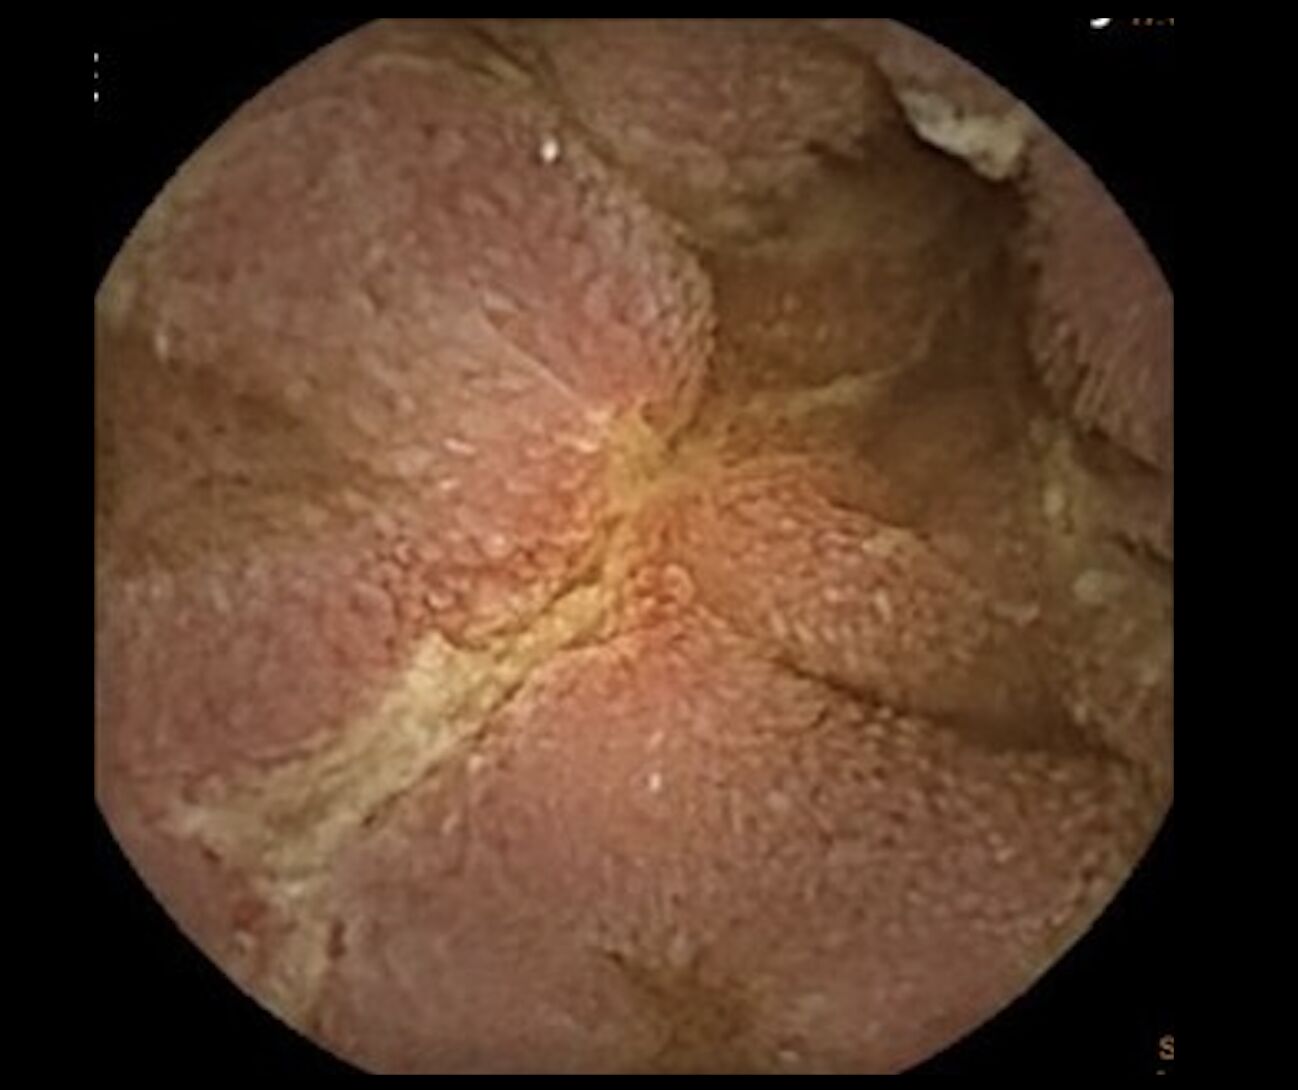

▲男子透過膠囊內視鏡才揪出禍首竟是少見的「克隆氏症」,小腸滿布潰瘍。

章振旺以該名男子為例,透過經膠囊內視鏡檢查,才發現小腸自空腸至迴腸處,有多處跳躍式病灶與縱向潰瘍,並綜合影像檢查、病理檢查等資訊排除其他可能性,結合臨床症狀表現,最終診斷為克隆氏症,幸運的是,經過類固醇與免疫調節藥物治療之後,目前情況已趨於穩定。

章振旺表示,小腸疾病較難以利用傳統腸鏡檢查一窺全貌,臨床上會仰賴膠囊內視鏡補足此一盲點,對克隆氏症早期發現與評估病灶嚴重程度有極大幫助。